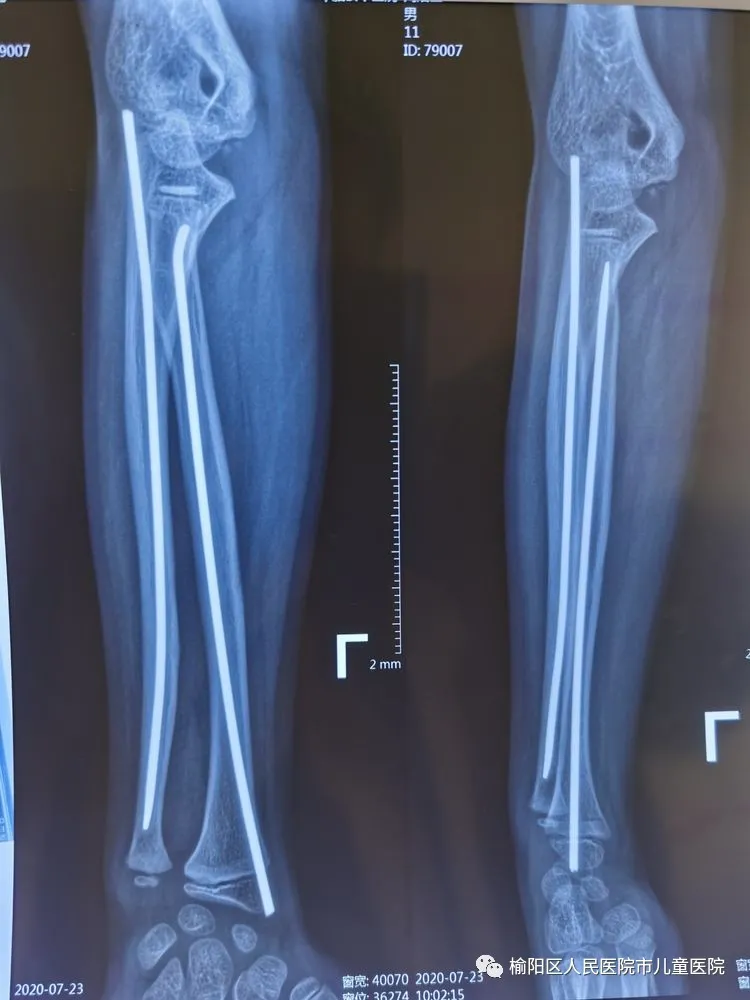

榆陽區(qū)人民醫(yī)院骨科——彈性髄內(nèi)針應(yīng)用分享

患兒12歲,因外傷致左尺橈骨骨折

復(fù)位外固定后家屬不滿意

在全麻下行彈性髄內(nèi)針微創(chuàng)閉合治療

0.5cm的微創(chuàng)小口

術(shù)后5個(gè)月,完美愈合。

彈性髄內(nèi)針治療小兒四肢骨折優(yōu)點(diǎn):手術(shù)時(shí)間短,創(chuàng)傷小,住院時(shí)間短,骨折愈合快,費(fèi)用低。